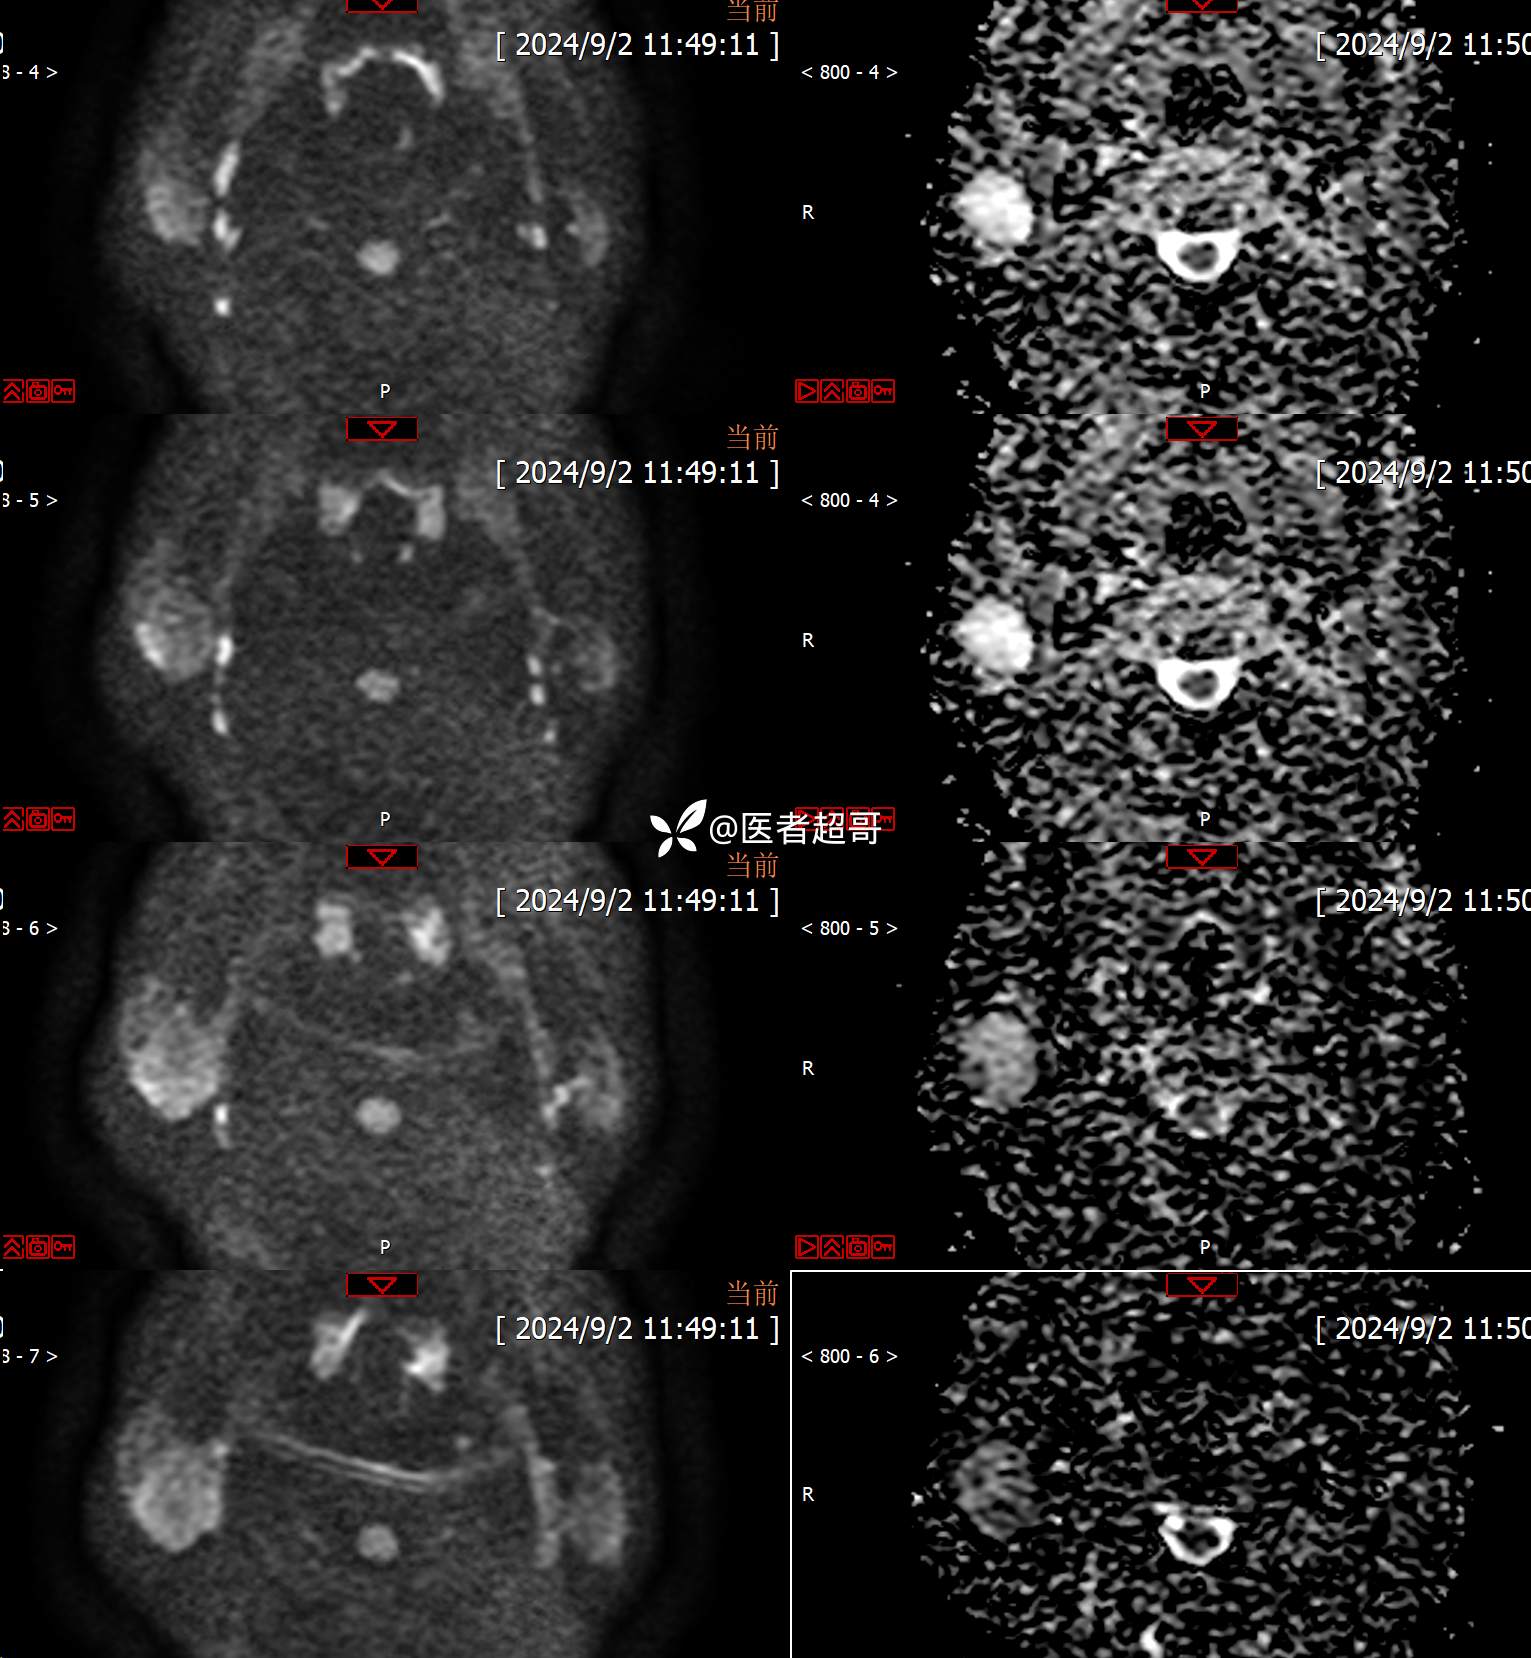

主诉:发现右腮腺肿物6个月。

现病史:患者于6个月前无明显诱因发现右侧腮腺区肿物,无疼痛,无局部皮肤破溃,无吞咽困难,无听力下降,无发热,无头痛头晕,患者自发病后在外未治疗,6天前于当地卫生院检查建议手术,为求手术治疗,来我院就诊,门诊以“腮腺肿瘤(右)”收入我院。患者自发病以来,神志清楚,精神可,饮食可,睡眠可,大便正常,小便正常,体重无明显变化。